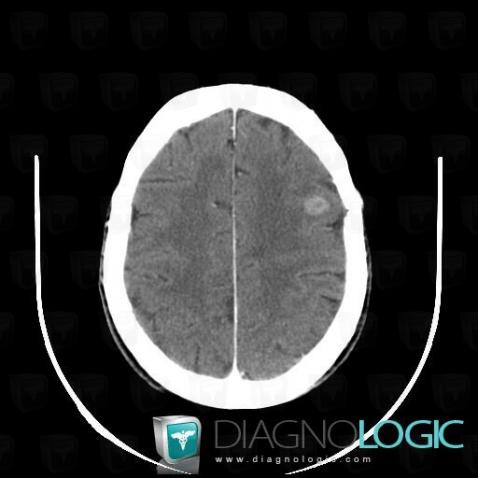

Metastasis, Cerebral hemispheres, CT

Here is the specific information in the key image above:

- Diagnosis Metastasis, Location(s) Cerebral hemispheres, with gamuts Intracerebral lesion with ring enhancement, Intracerebral CSF intensity lesion, Multifocal intracranial lesions, Intracerebral mass